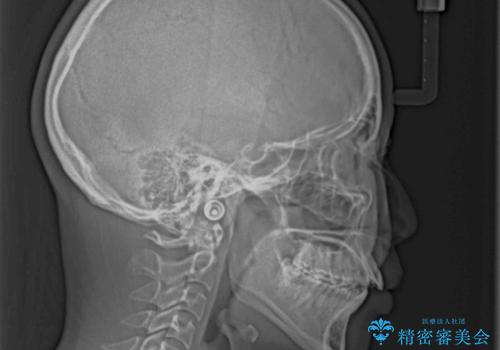

飛び出した前歯 インビザラインを用いた抜歯矯正治療

- 前方に飛び出した前歯を気にして来院された患者様です。

上下前歯同士の距離が離れているため、上顎左右第一小臼歯2本を抜歯することで前突を改善することとしました。

しかしながら、左右ともに側切歯が矮小歯であるため、矯正治療で矮小歯前後にスペースを作り、矯正治療後にオールセラミッククラウンにて補綴治療を行うこととしました。